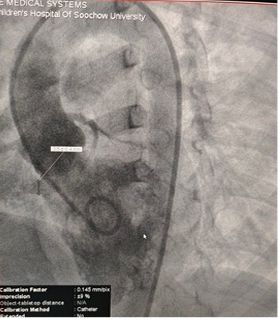

Selected MemoSorb ABFDQ-II 9 occluder based on intraoperative angiography and echocardiographic assessment.